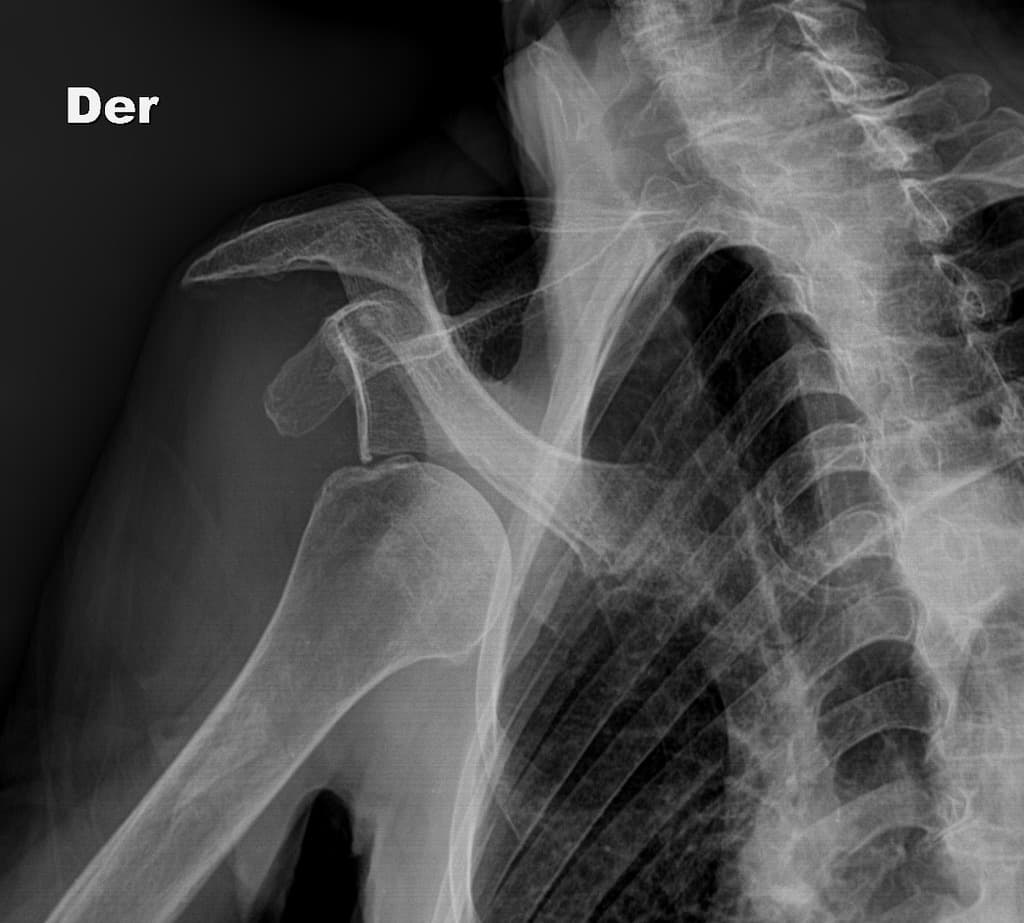

Trật khớp vai ra trước. Trục khớp ổ chảo - cánh tay bình thường. Không thấy trật khớp. THẢO LUẬN: Hình ảnh X-quang khớp vai phải cho thấy tình trạng trật khớp ra trước, đã được nắn chỉnh thành công.

Trật khớp vai ra trước thường xảy ra sau khi ngã với cánh tay ở tư thế giang và xoay ngoài. Chỏm xương cánh tay bị di lệch ra trước, vào trong và thường là xuống dưới so với ổ chảo. Đánh giá X-quang có vai trò quan trọng không chỉ để chẩn đoán mà còn để xác định các tổn thương xương đi kèm có thể ảnh hưởng đến việc điều trị và độ vững của khớp.